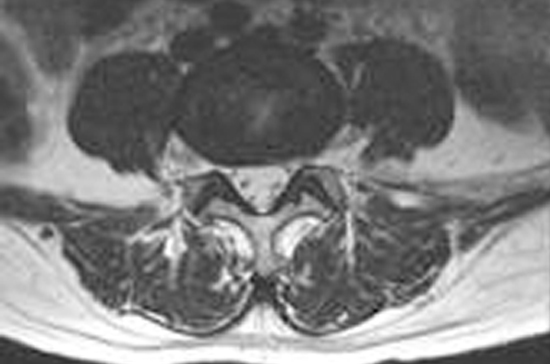

양방향 척추내시경 신경감압술

양방향 척추내시경 신경감압술은 약 4㎜ 가량 작은 구멍을 두군데 뚫어 내시경을 삽입해 협착된 부위를 제거하는 수술법입니다.

한쪽은 내시경을 삽입해 정확한 원인을 찾는 동시에, 다른 한쪽으로는 수술기구를 삽입해 척추관협착증의 주된 원인인 인대와 관절의 골극을 제거하는 첨단 수술 기법입니다.